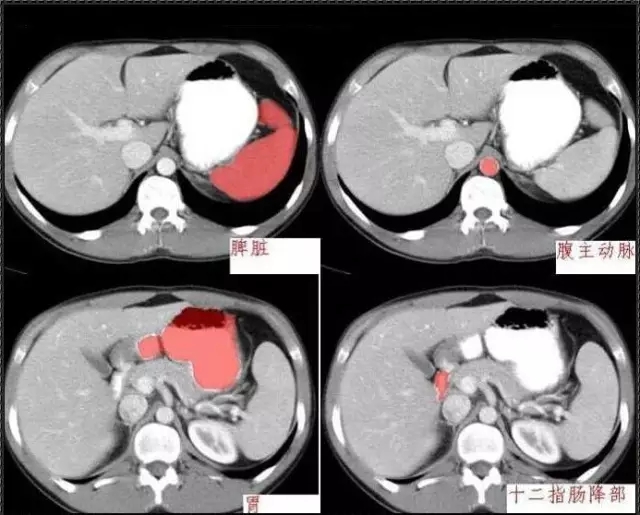

秒懂:腹部 CT 看這篇就夠